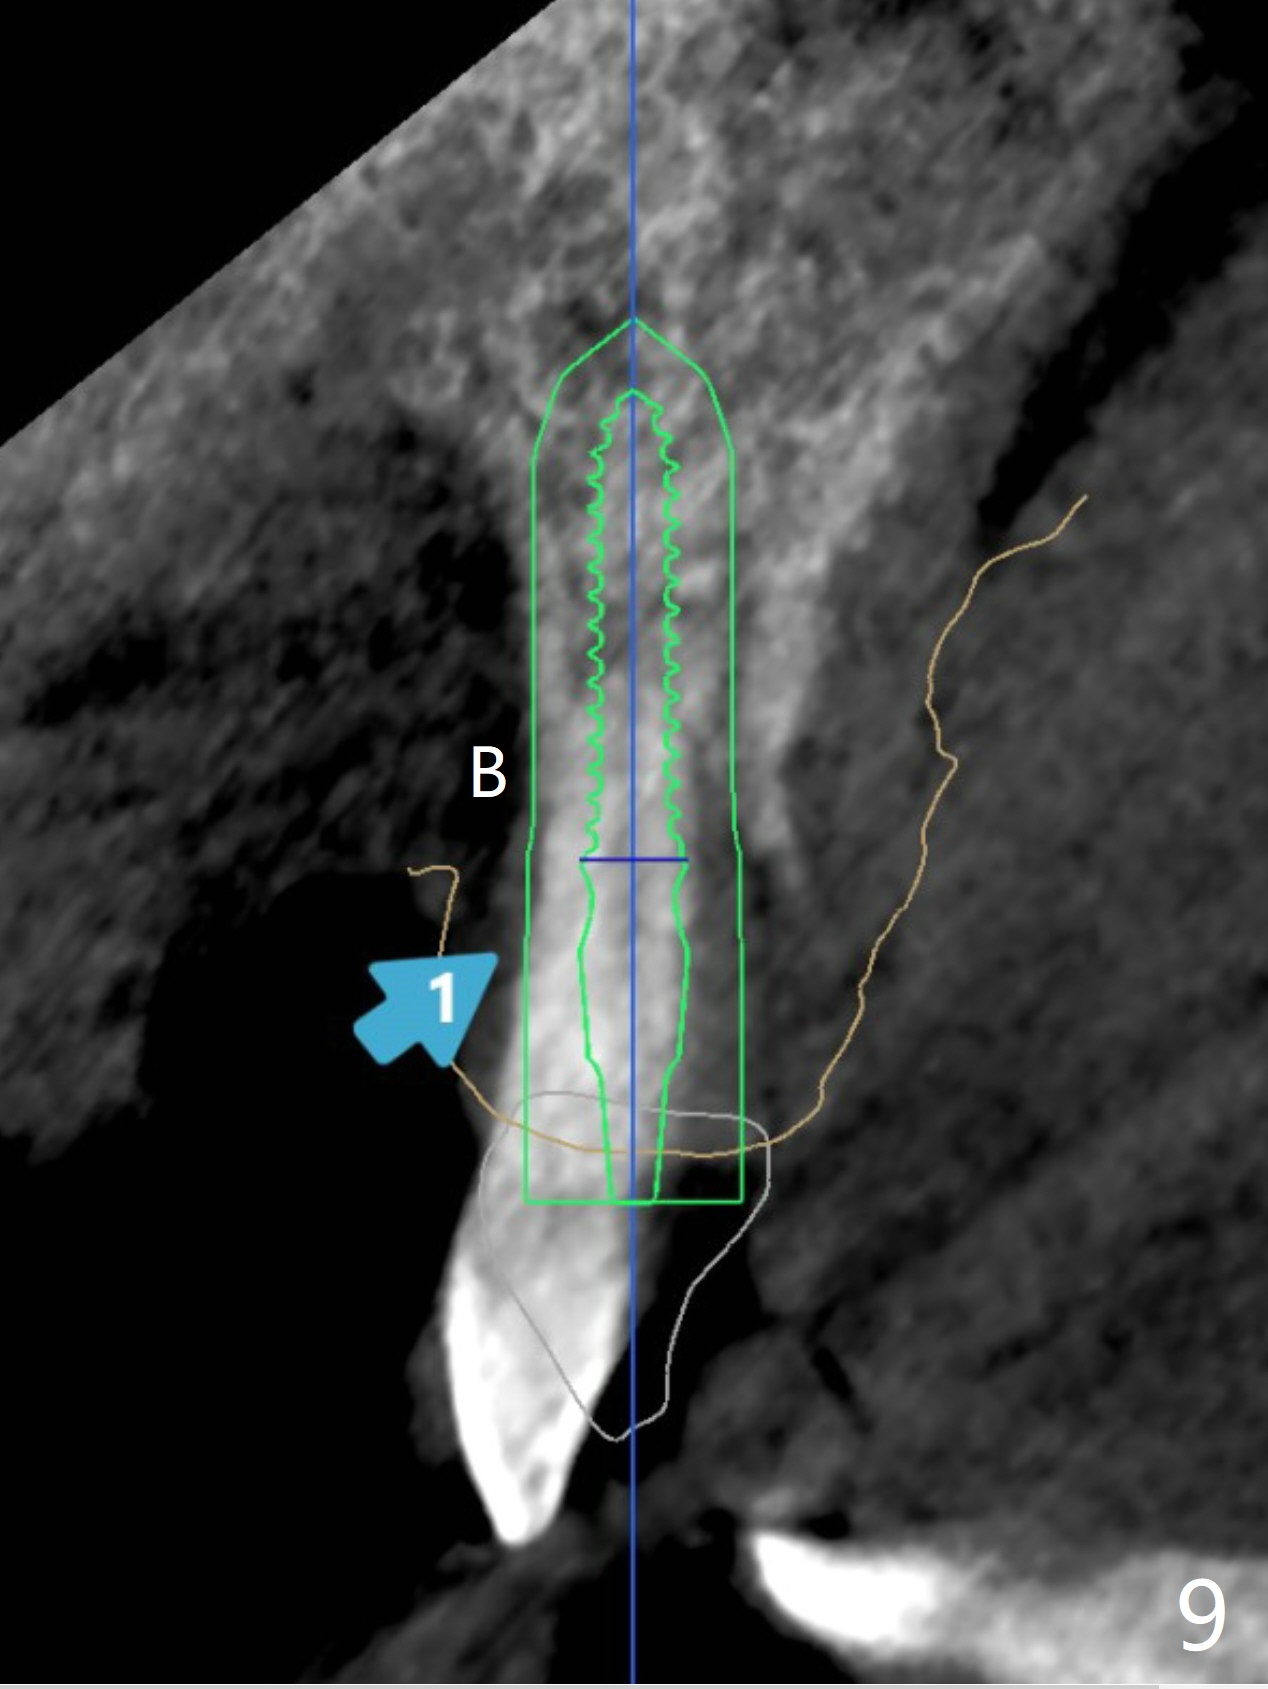

植体不侵犯颊侧骨壁(导板,细植体何等重要),患牙(颊侧移位)不再挤压牙龈,牙龈会长长(恢复正常长度),可能在貌似牙龈退缩大多数情况下,不必植龈,即种就可以了。基台面向切缘,可以长些,临时和永久牙冠不容易脱落。

自然牙冠       Last     Next     尖牙即种  修复  Xin Wei, DDS, PhD, MS 1st edition 06/01/2021, last revision 06/14/2021